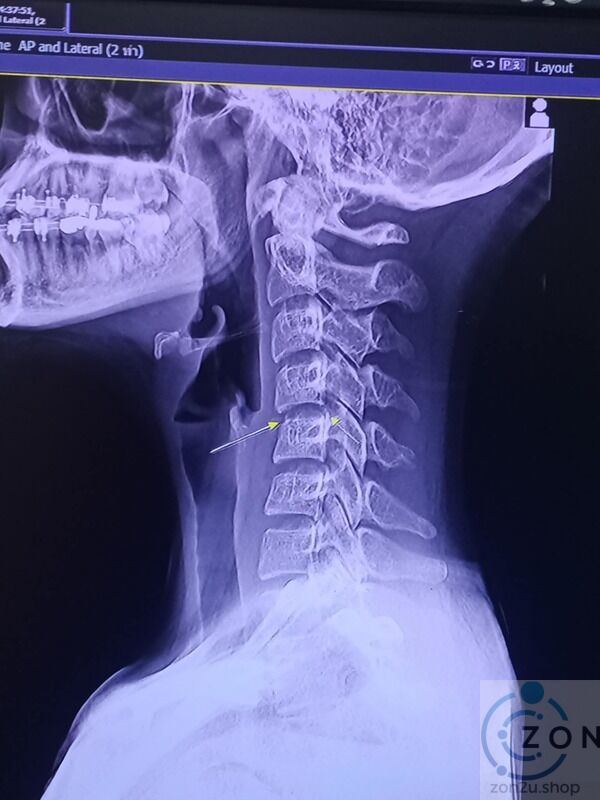

Pada bulan November 2024, Phing, yang mengalami sakit bahu, memutuskan untuk mendapatkan urutan di sebuah pusat urut. Selepas menjalani urutan yang melibatkan teknik memutar leher, dia mula merasakan kesakitan yang teruk. Dalam beberapa hari, keadaan kesihatannya semakin merosot dengan kelemahan di lengan dan akhirnya paralisis separuh badan. Tidak lama kemudian dia meninggal dunia.

Pakar neurologi mengingatkan bahawa urutan leher yang tidak betul boleh menyebabkan kecederaan serius, termasuk strok dan paralisis. Statistik menunjukkan bahawa teknik urutan yang melibatkan tekanan berlebihan pada leher adalah berisiko, terutama bagi individu dengan sejarah masalah kesihatan tertentu.